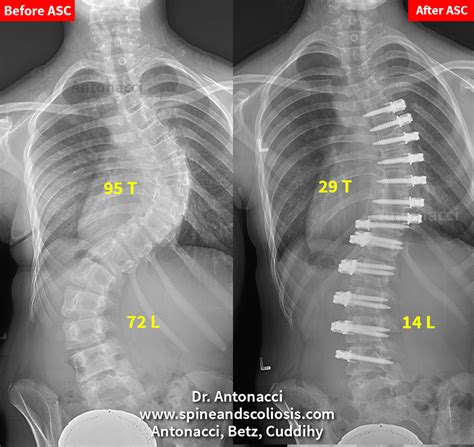

• X-rays: Imaging tests, such as X-rays, are used to measure the Cobb angle and determine the severity of the curvature.

• Surgery: In severe cases, surgical intervention may be necessary to correct the curvature and stabilize the spine. Common procedures include spinal fusion and instrumentation.